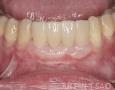

Baseline